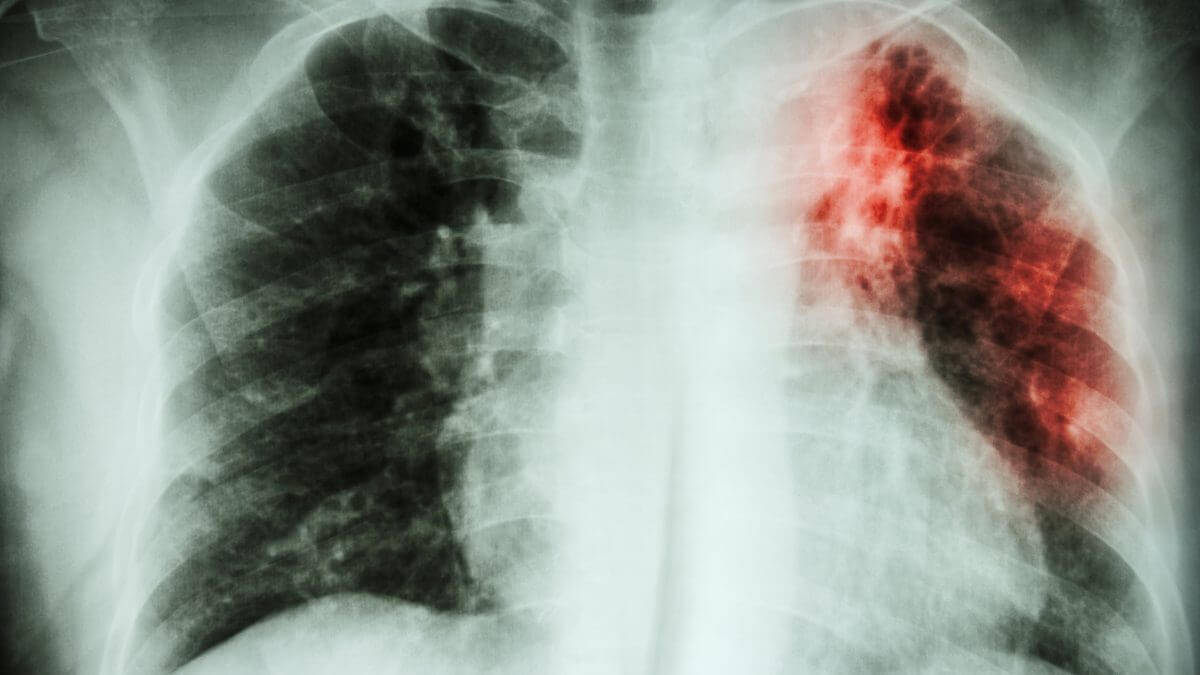

O que é a tuberculose extensivamente resistente?

A tuberculose extensivamente resistente é uma forma grave de tuberculose resistente a múltiplos medicamentos. A resistência a múltiplos medicamentos ocorre quando as bactérias desenvolvem resistência a pelo menos dois dos medicamentos mais potentes e comuns no tratamento da doença, como isoniazida e rifampicina, além de resistência a pelo menos um dos medicamentos de segunda linha.

A tuberculose resistente a medicamentos é uma preocupação significativa de saúde pública, pois torna o tratamento mais difícil e prolongado, aumentando os riscos de complicações e disseminação da doença.